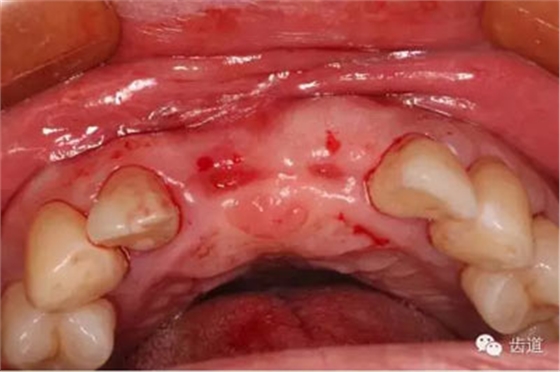

臨床檢查:

患者高位笑線,薄牙齦型。

11,21缺失。因外傷,導(dǎo)致11骨高度降低。

患者不愿才用自體骨移植,遂建議采用同種異體骨骨塊(皮質(zhì)骨)進(jìn)行骨環(huán)手術(shù)。 種植手術(shù):